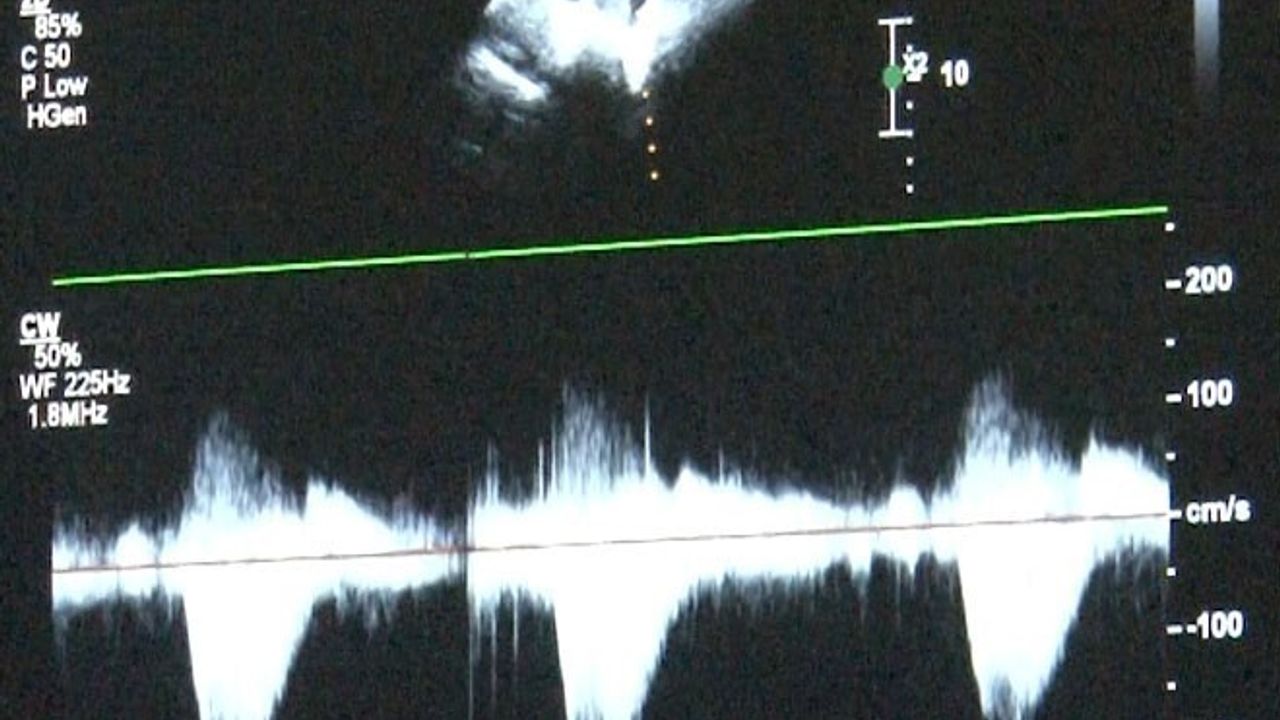

Erken tanı ve fetal ekokardiyografi

Kanuni Sultan Süleyman Eğitim ve Araştırma Hastanesi Çocuk Kardiyoloji Uzmanı Uzm. Dr. Damla Gökçeer Akbulut ve Sultangazi Haseki Eğitim ve Araştırma Hastanesi Çocuk Kardiyoloji Uzmanı Dr. Canan Yolcu erken tanının hayat kurtardığını aktarıyor. Fetal ekokardiyografi ile anne karnındayken doğumsal kalp hastalığı tespit edilebiliyor; böylece doğum sonrası erken müdahale şansı sağlanıyor. Uz. Dr. Gökçeer Akbulut, Sağlık Bakanlığı verilerine göre her yıl bin canlı doğumdan 8'inde doğumsal kalp hastalığı görüldüğünü hatırlattı.